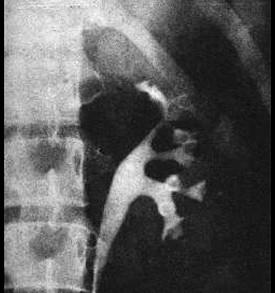

问题 关于泌尿系结核,哪项叙述是正确的 ( )

选项 A、肾结核的主要治疗是肾切除 B、有挛缩膀胱的男性病人适宜作肠膀胱扩大术 C、血尿常是最早出现的症状 D、多有明显的腰痛 E、肾结核病原在肾,症状在膀胱

答案 E